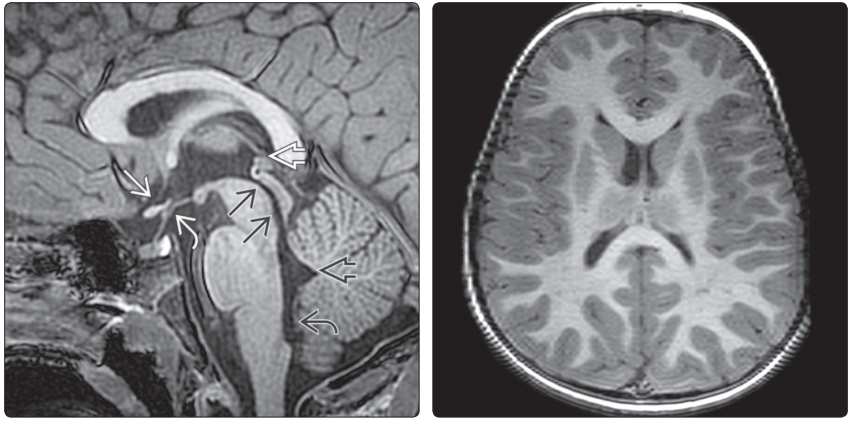

(左图)第三、第四脑室MR矢状中线位T1WI示:第三脑室视交叉隐窝→、漏斗隐窝↪、松果体上隐窝⇒,形态正常;中脑导水管→,正常情况下其近端窄于远端;第四脑室的尖顶(fastigium)和Magendie 孔↪,矢状中线位显示好。(右图)MR横断位T1WI示(侧脑室前角和三角区水平):包括细长的枕角在内的侧脑室正常形态

(左图)横断位LFAIRMRI示:第三脑室前隐窝→,正常呈裂隙状。另外,枕叶内侧高信号分别是指环形连接的左枕角↪、囊肿样结构的右枕角 ⇒。(右图)冠状位LFAIR MRI示:枕叶小灶高信号→显示的是环形连接的左枕角,不能误诊为发育不良或损伤

(左图)MR冠状位T;WI示(侧脑室体部→和枕角水平↪):颞角呈裂隙状,位于海马内侧喙缘(rostralto the medial aspects of the hippocampi)。(右图)冠状位FLAIR MRI示:正常儿童三脑室↪,呈裂隙状。正常额角→狭窄,双侧稍欠对称。颞叶内侧高信号⇒显示的是胚胎性颗角的正常残余